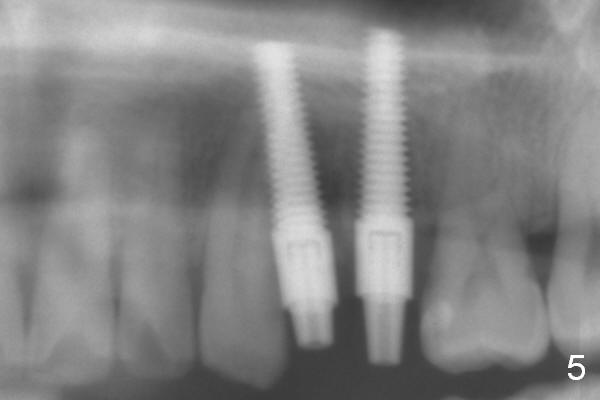

Taking 2 additional PAs with sensor 1 is frustrating (Fig.1,2), no apices shown.  Osteotomy is done smoothly with 2 mm pilot drill at 20 mm, 2.5 mm reamer at 17 mm, and 3 mm reamer at 14 mm and 4.5x20 mm tap at 17 mm.  The 1st intraop PA is taken with sensor 1 when 2 of 4.5x20 mm implants are placed (Fig.3); the implant at #12 is close to the root of the tooth #11.  The 2nd PA is taken with sensor 2: the apex of #11 touches the implant at #12 (Fig.4).  There is no separation when panoramic X-ray is taken (Fig.5).  Effort is exerted to re-direct the osteotomy twice (Fig.6: tap; Fig.7: implant) without success.  When the implant is removed, a PA is taken; it appears that the root of the tooth #11 has no damage (Fig.8).  To obtain the best recovery, socket preservation is carried out with 50/50 cortical/cancellous allograft mixed with Osteogen (Fig.12 *) and Collagen Dressing (Fig.9: #12).  A 2 (or 3)-unit provisional bridge (Fig.10: #12,13) is fabricated over the implant (Fig.9 I)/abutment (A) to cover these 2 sockets.  After acid etching #11 D surface (Fig.9 >) and relining (Fig.11 *), the provisional bridge is bonded to the tooth #11 (Fig.11,12 black >) so that bone graft will be less likely dislodged.